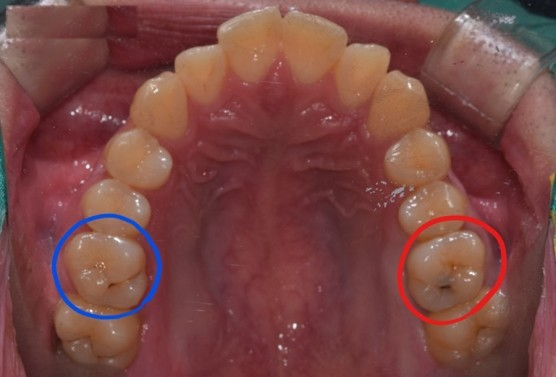

두번째 케이스의 환자분입니다.

까만점이 바로 딱 보이죠?

양쪽 충치의 모습이 보입니다.

파란색 치아는 치료를 하지않고 경과관찰을 하기로 한 충치이고

빨간색 치아는 치료를 진행한 충치입니다.